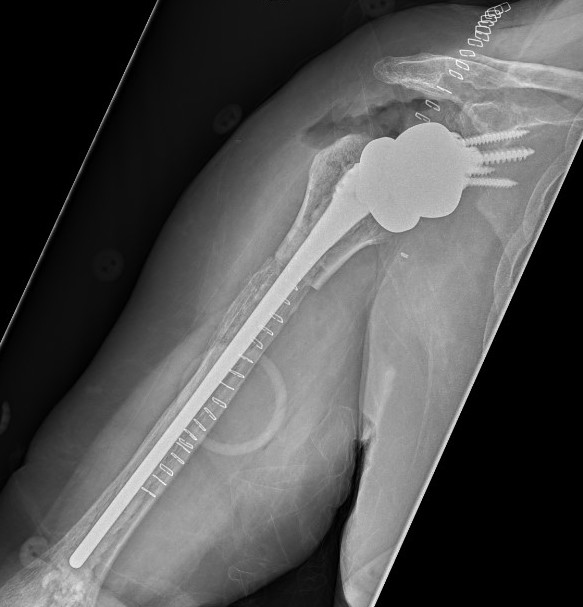

Revision Humeral Component

Technique

- often need long stem

- often use cement in revision circumstance

May need proximal humerus allograft

Sanchez - Sotelo et al. JBJS Am 2017

- 26 patients undergoing revision to reverse with bulk proximal allograft

- average time to union 7 months

- one patient required bone grafting to obtain union